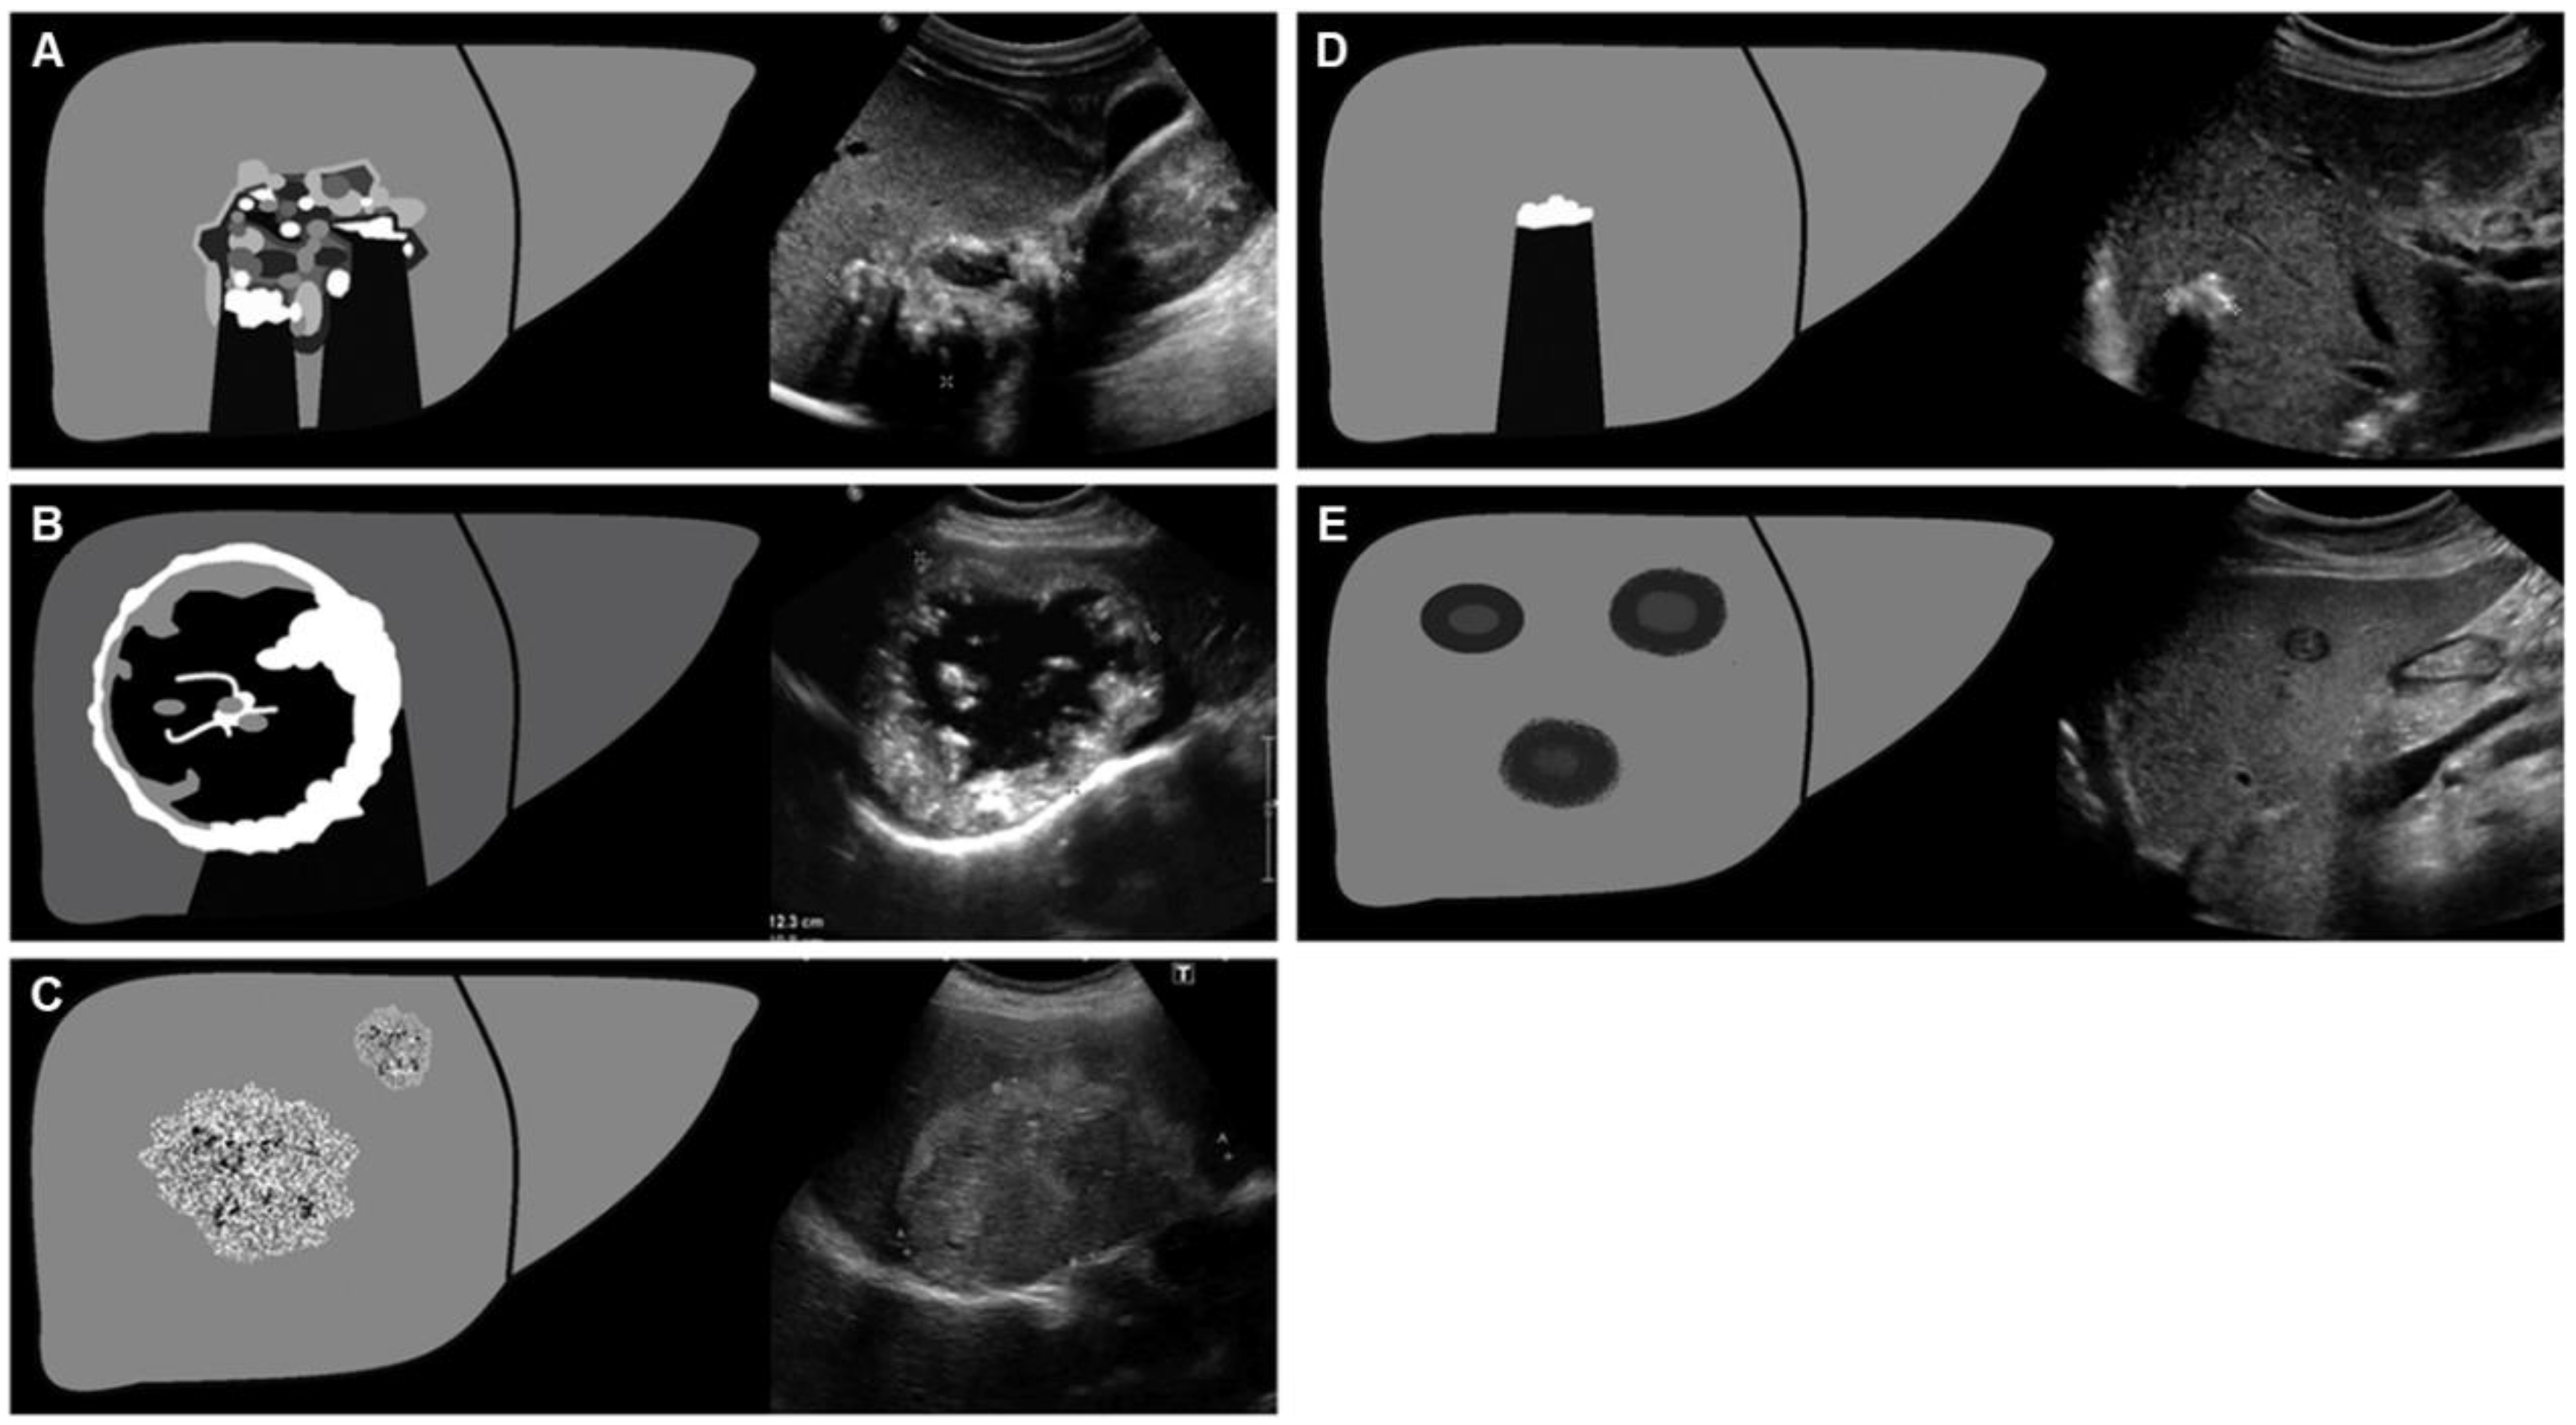

Besides the US, computed tomography (CT) is presently the preferred diagnostic imaging among the available methods, as it is capable of detecting the highest number of lesions and clearly distinguishing characteristic calcifications [111,112]. Abdominal CT is more suitable for identifying calcifications and preoperative assessment. CT scan primarily relies on the determination of lesion size, rather than on the accurate assessment of AE proliferation and infiltration activity. In 2016, Graeter et al. [113] proposed five classifications for CT imaging of hepatic alveolar echinococcosis (Figure 5). Type I: diffuse infiltrating, Type II: primarily circumscribed tumor-like, Type III: primarily cystoid, Type IV: small-cystoid/metastatic, Type V: mainly calcified. After conducting a retrospective analysis of 228 patients with hepatic alveolar echinococcosis, they revealed that the most frequently encountered CT morphological pattern was the diffuse infiltration pattern (Type I), followed by the primarily circumscribed tumor-like appearances (Type II). The mainly calcified appearance (Type V) was observed less frequently. The E. multilocularis Ulm classification for computed tomography (EMUC-CT) offers the basis for the systematic description of the CT morphology of AE lesions of the liver [114]. A study has shown that there is a close correlation between the patterns of AE according to the EMUC-CT classification and the different histological patterns of AE infections [79]. The CT types mark consecutive stages of infection, which progress over time. The classification of calcifications in AE observed on CT is shown in Figure 6.

Figure 6. Patterns of calcification [124]. The calcification of AE in CT images is classified into five stages: no calcifications; feathery calcifications; focal calcifications; diffuse calcifications; calcifications primarily at the edge and central calcification.